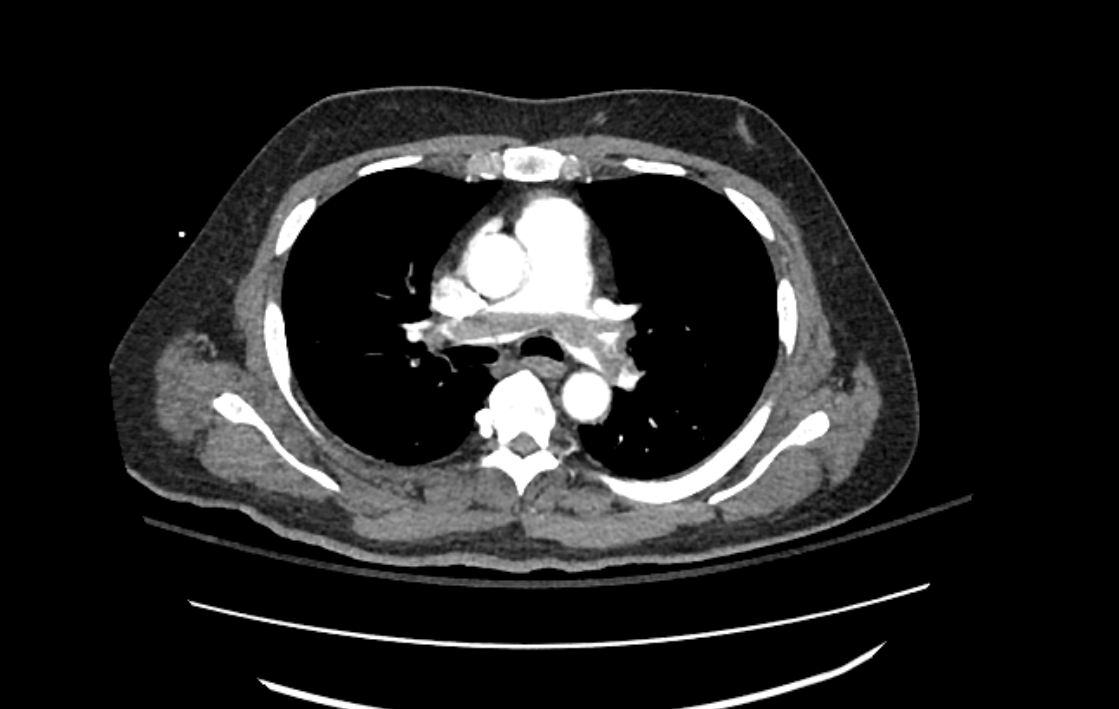

A 45 yo male presents after syncope in rehabilitaion center. He is 3 weeks post operative spinal surgery. He c/o dyspnea. A cat scan is done. What's the diagnosis. Scroll down for answer.

Answer: Saddle pulmonary embolism

CTA Chest:

Preferred Test! Highest sensitivity.